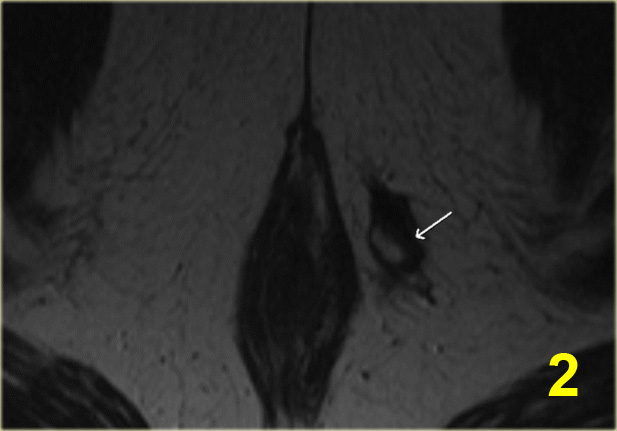

Bệnh nhân này đã được chẩn đoán trước đó là rò liên cơ thắt, với tổn thương niêm mạc ở vị trí 1 giờ.

Trong lòng đường rò có một cấu trúc dạng tuyến tính với tín hiệu thấp.

Đây là chỉ Seton đã được đặt vào để điều trị đường rò.